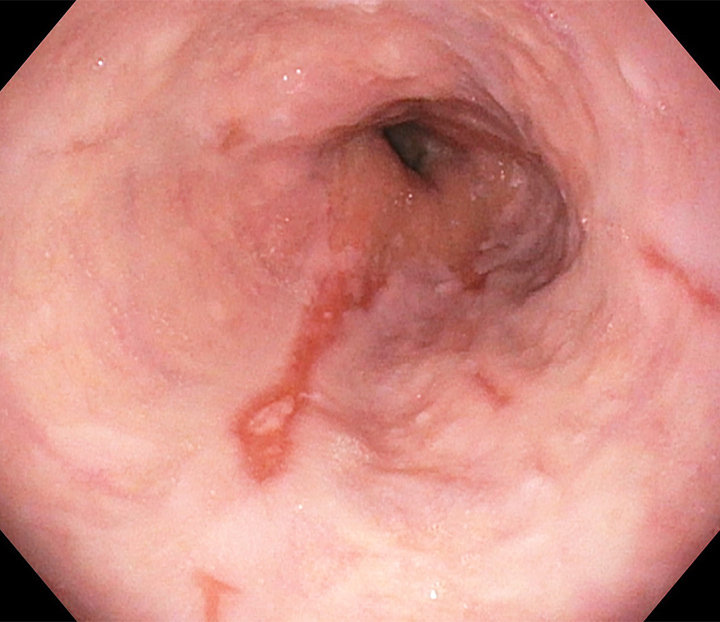

逆流性食道炎

逆流性食道炎とは、胃の内容物が食道に逆流することで、食道の粘膜に炎症が起こる病気です。主な症状は「胸やけ」や「酸っぱい液がこみ上げる感じ(呑酸/どんさん)」で、横になるときや食後に悪化することがよくあります。

- 視鏡検査(胃カメラ):炎症の有無を確認

びらん(ただれ)が見つかる場合は「びらん性」、見られない場合でも症状があれば「非びらん性(NERD)」と診断されます。